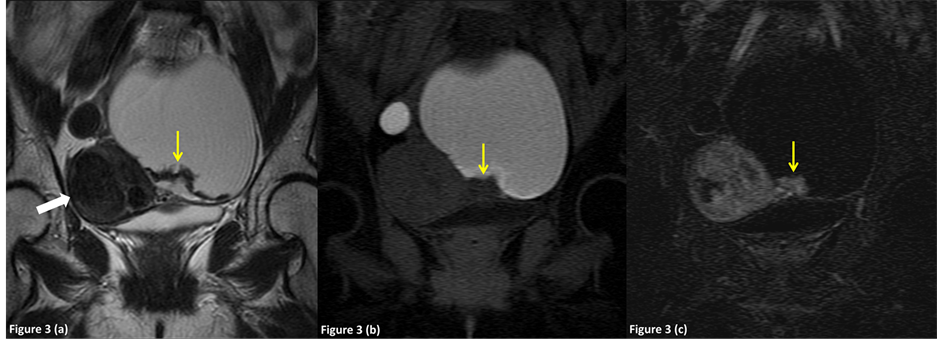

Figure 3. A 48-year-old female was diagnosed preoperatively with an endometrioma complicated with clear cell adenocarcinoma in the left ovary, which was correctly diagnosed on preoperative MR imaging (group 2). (a) Axial T2-weighted image shows a diffusely hyperintense right adnexal mass (arrow) and a hyperintense mural nodule in the hypointense cyst wall. Hypointense uterine leiomyoma was noted in the uterine body (white arrow). (b) Axial fat-suppressed T1-weighted image shows a hyperintense adnexal mass and a hypointense mural nodule (arrow). The attached angle of the mural nodule to the cyst wall was 115.3 degrees (obtuse angle). (c) Axial subtraction image shows intense enhancement of the mural nodule (arrow). Note the enhanced uterine leiomyoma in the uterine body (white arrow).

On T1-weighted MR images, the internal contents of the lesions showed high signal intensity in 152 (100%), 6 (67%) and 17 (100%) lesions in groups 1, 2 and 3, respectively (Figure 2, Figure 3). On T2-weighted MR images, the internal contents of the lesions showed shading in 73 (48%), 4 (44%), 7 (41%) and 1 (100%) in groups 1, 2, 3 and 4 s respectively (Figure 2, Figure 3). The mean maximum thickness of the wall and septum was 3.1 ± 0.7 mm and 2.9 ± 0.8 mm in group 1, 2.8 ± 0.4 mm and 3.2 ± 0.8 mm in group 2, 2.6 ± 0.8 mm and 3.2 ± 1.0 mm in group 3, and 2 mm and 0 mm in group 4; there were no significant differences among the groups. The p-values between groups 1 and 2, groups 1 and 3 and groups 2 and 3 in the maximum thickness of the wall were 0.21, 0.15 and 1.83, respectively. The p-values between groups 1 and 2, groups 1 and 3 and groups 2 and 3 in the maximum thickness of the septum were 1.65, 1.83, and 2.82, respectively (unpaired t-test with the Bonferroni correction).

On T1-weighted images, the mural nodules were hyperintense in one lesion (14%) in group 1 (Figure 2) and one (5%) in group 3, and hypointense in 6 (86%), 16 (100%) and 21 (95.5%) lesions in groups 1, 2 and 3 (Figure 3, Figure 4), respectively. On T2-weighted images, the mural nodules were hypointense in 7 (100%), 2 (13%) and 13 (59%) lesions in groups 1, 2 and 3 (Figure 2), respectively, and hyperintense in 0 (0%), 14 (88%) and 9 (41%) lesions in groups 1, 2 and 3 (Figure 3, Figure 4). In our study, only 9 of 26 cysts with enhanced nodules (34.6%) were diagnosed as pathologically malignancy.